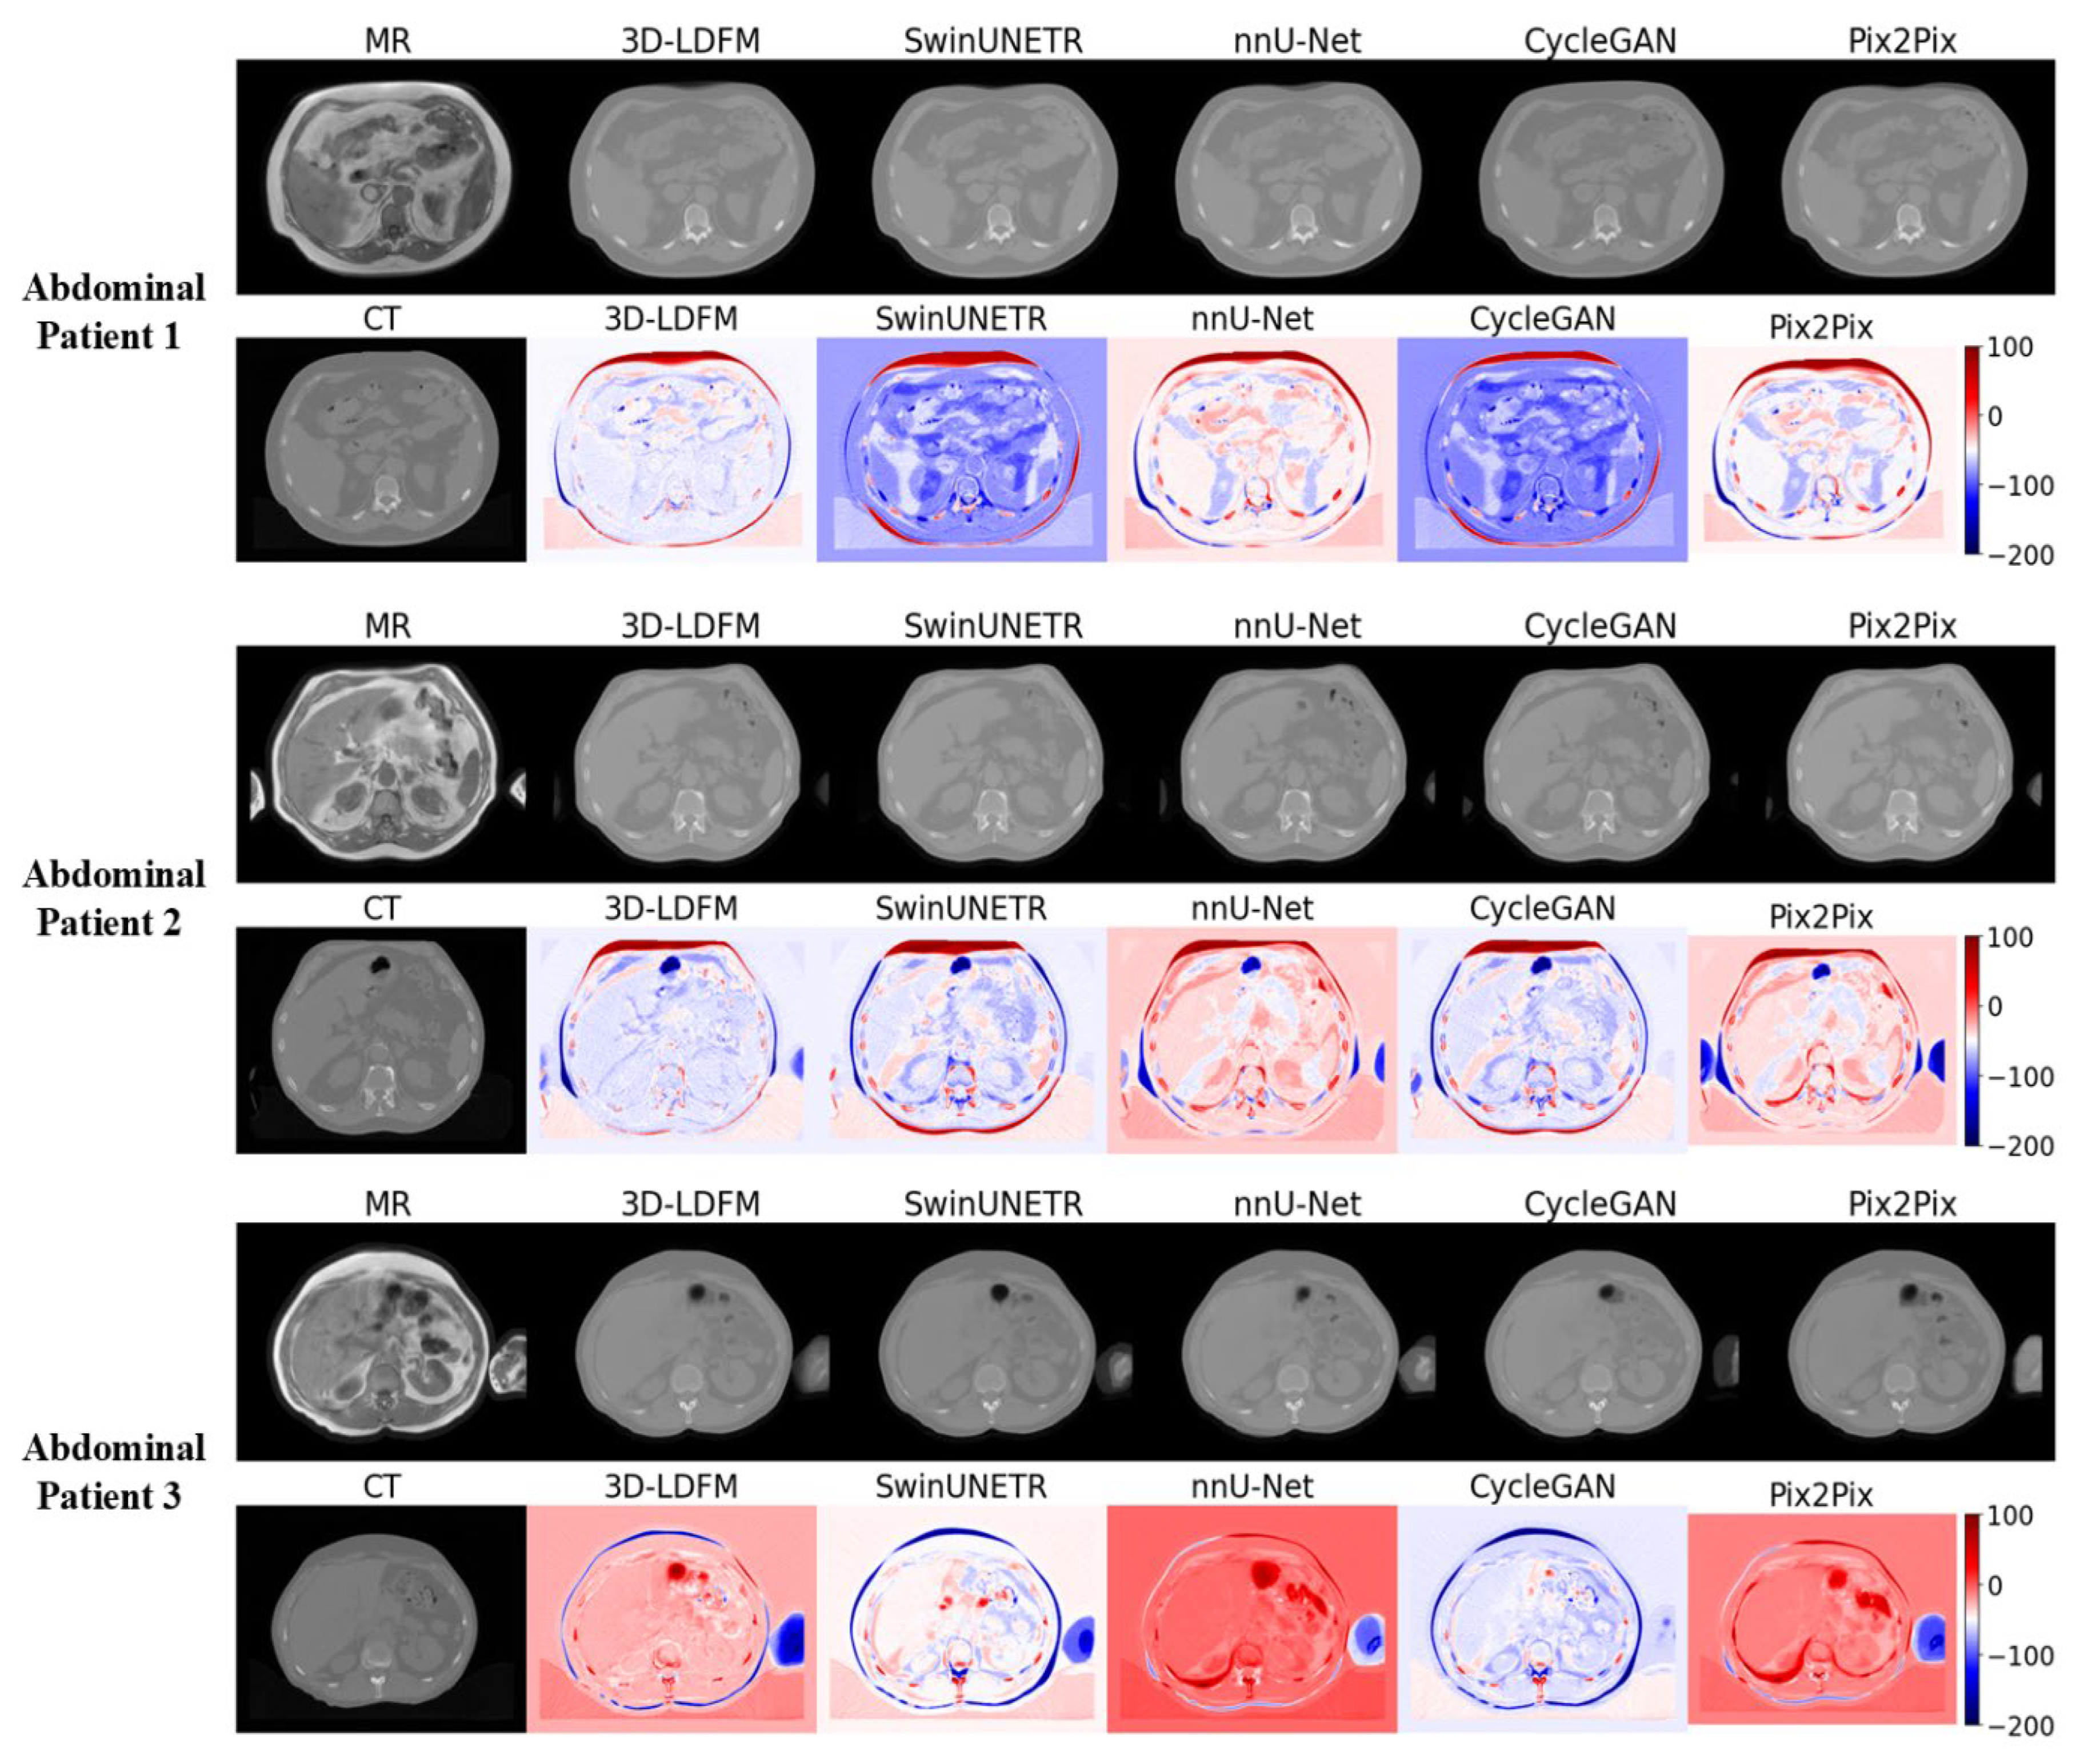

4.2. Assessment and Error Mapping